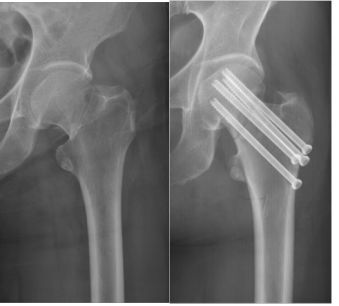

55岁手术后次日下地走路,45天愈合(具有临床愈合特征和X光愈合特征)这是愈合时间最短的股骨颈骨折